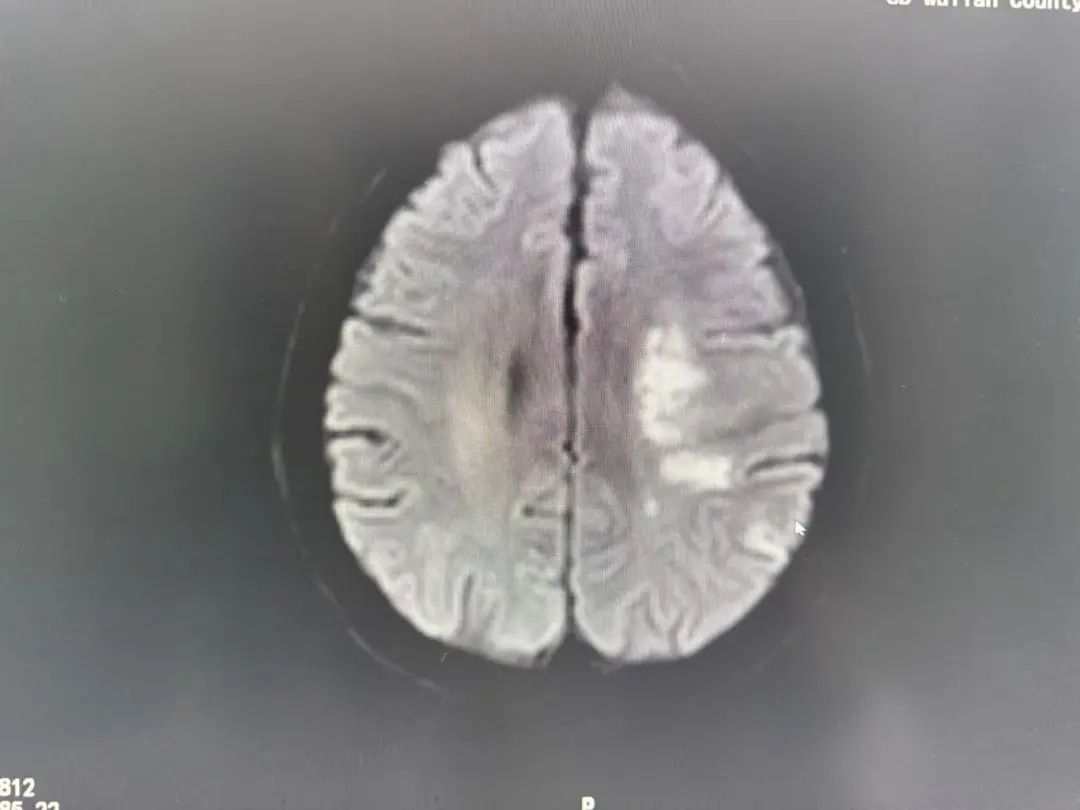

"左侧大脑中动脉闭塞!"

头颈部CTA检查揭开了更凶险的真相:

多发性脑梗死:左侧大脑关键区域受损

血管危机:左侧大脑中动脉闭塞,血流几乎中断

罕见盗血现象:锁骨下动脉重度狭窄,导致血流“偷走”了脑部的供血